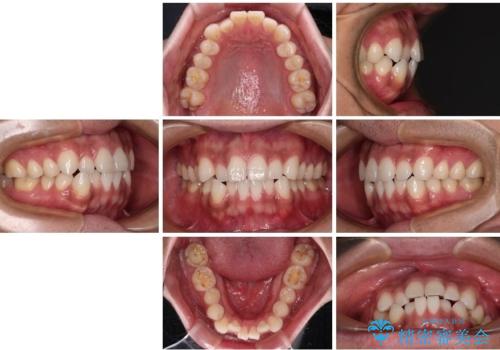

目立たない装置でデコボコを改善 ハーフリンガルによる矯正治療

- 30代男性

- 1年4ヶ月

- 100万円(税込)費用は治療当時の料金となります

一年と数か月で矯正を終えることができました。

下顎前歯部には後戻り防止のワイヤーを装着しています。